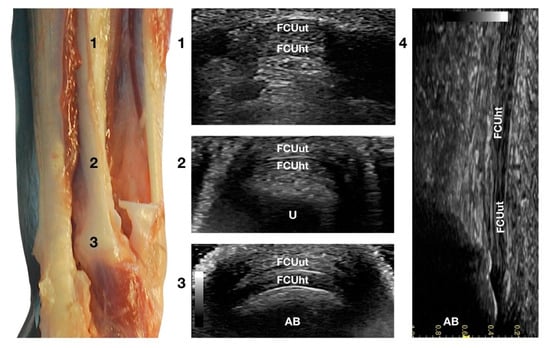

3.3.1. Flexor Carpi Ulnaris Tendon Ultrasonographic Anatomy (FCUt)

The two tendinous portions of the Flexor Carpi Ulnaris tendon (FCUt) were visible and easily palpated at their attachment to the accessory carpal bone (Figure 1c). A longitudinal approach starting distally to the tendinous bone attachment, easily palpated, and progressing proximally up to the tenomuscular junctions, made the identification of these two structures easy (Figure 6).

Figure 6.

Palmar carpal face centred on the Flexor Carpi Ulnaris tendon. Part of the distal attachment of the FCUut covering the FCUht was removed to show the thicker, deeper portion. At the ulnar notch level (2), the FCUt is a broad and flattened elliptical tendon subdivided into two nearly equal parts by a thin hyperechoic line. Some fat separates the tendon from the deeper osseous contour of the distal portion of the ulna (U). Proximally, at the tenomuscular junction (1), the combination of the two-part forms a rounder and narrower tendon. The tendon becomes thinner and more expansive due to the insertion based on the accessory carpal bone (AB) (3). On the longitudinal scan plane (4), the prominent fibrillar pattern of the tendon components is visible.

The ulnar head of the Flexor Carpi Ulnaris tendon (FCUut) appeared as a thin hyperechoic band that encroached on the thicker humeral head tendon (FCUht). They ended in a close relationship at the proximal aspect of the accessory carpal bone. The two tendinous parts were more clearly identified on the transverse scan plan. The combined tendons appeared as a flat elliptical hyperechoic structure, divided into two nearly equal bands by a thin hyperechoic line. Proximally, the united tendon was thicker and less wide; when extending distally, the tendon became elliptical and finally oval with a decreased thickness at the attachment site on the top of the accessory bone.

Flexing and extending the carpus, and stressed mediolateral movements could be used to evaluate subluxation, partial avulsion, adhesion, and reduced range of motion. The dynamic evaluation was more complete with the paw in elevation.